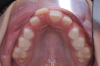

Fig 9. Clinical situation after completion of phase 1 treatment that allowed the impacted maxillary right central incisor to be properly positioned in the arch, frontal view (Fig 9) and occlusal view (Fig 10).

Fig 10. Clinical situation after completion of phase 1 treatment that allowed the impacted maxillary right central incisor to be properly positioned in the arch, frontal view (Fig 9) and occlusal view (Fig 10).